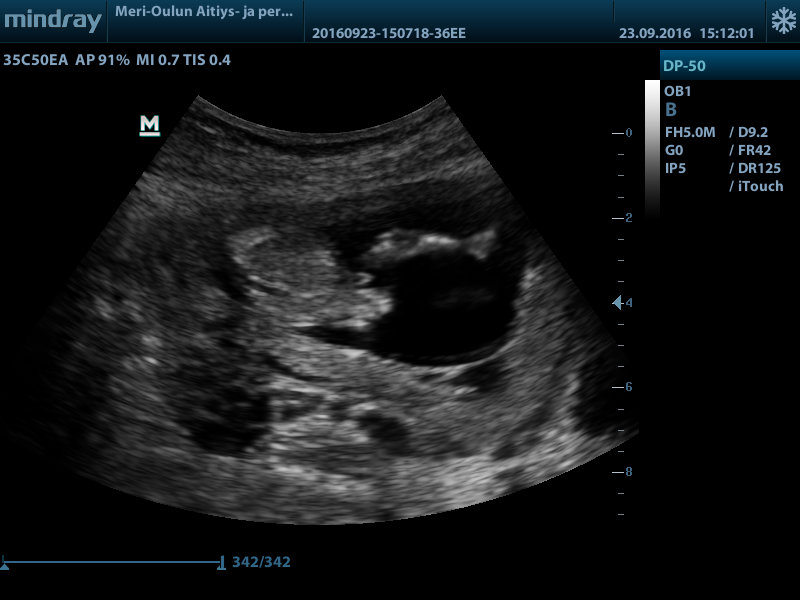

Hi! Would love your thoughts regarding the gender. Boy or girl? (And maybe why, I'm really new at this.. )

Top of the baby isn't the best for nub guessing but at 13 weeks girl parts wouldn't be so...large... At that gestation. I'm a few of the pictures I am almost positive I see testicles too so my guess is boy :) will actually be a little shocked if you hear girl please update when you know!